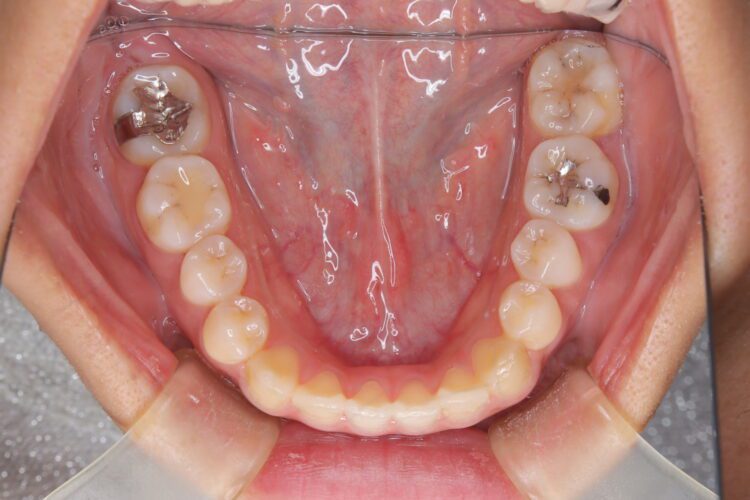

受け口の改善を主訴にご来院された患者様です。

軽度の下顎前突と診断し、マウスピース矯正装置(インビザライン)を用いて治療を行うこととしました。